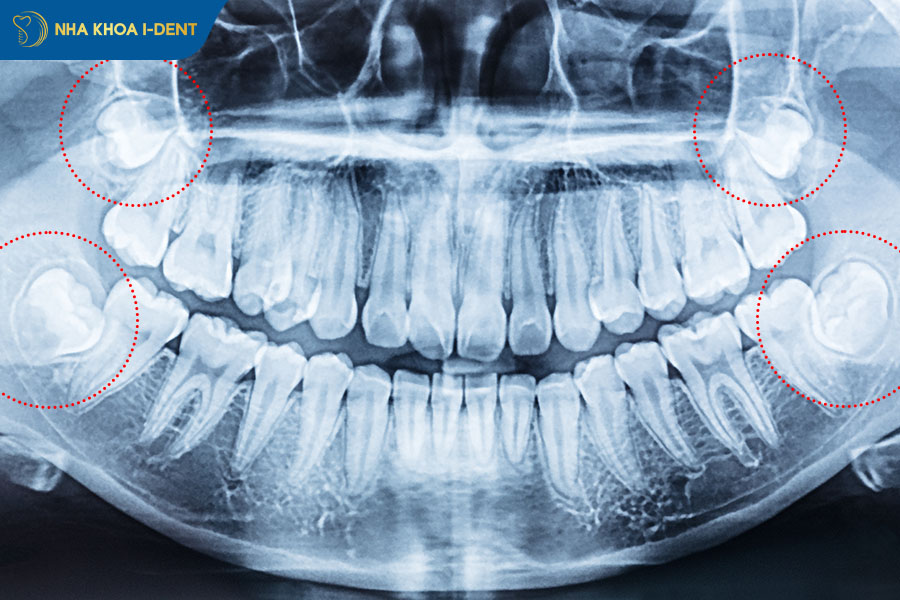

- X-quang phát hiện chân răng số 7 đang bị chèn ép, mất xương xung quanh thân răng số 8, hoặc hình ảnh bóng mờ bất thường (nghi u nang).